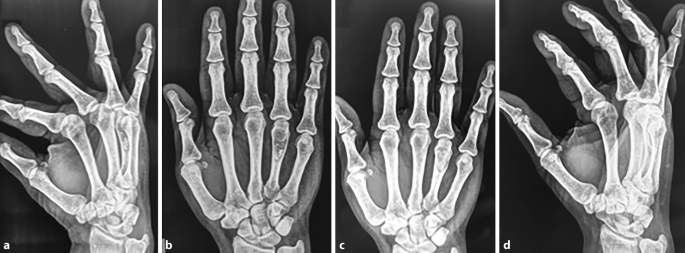

Enchondroma Hand

Enchondroma - Azouz Hand SurgeryAzouz Hand Surgery Enchondromas - Pathology - Orthobullets LearningRadiology- Enchondroma Enchondroma-of-hand LearningRadiology- Enchondroma Enchondroma Hand